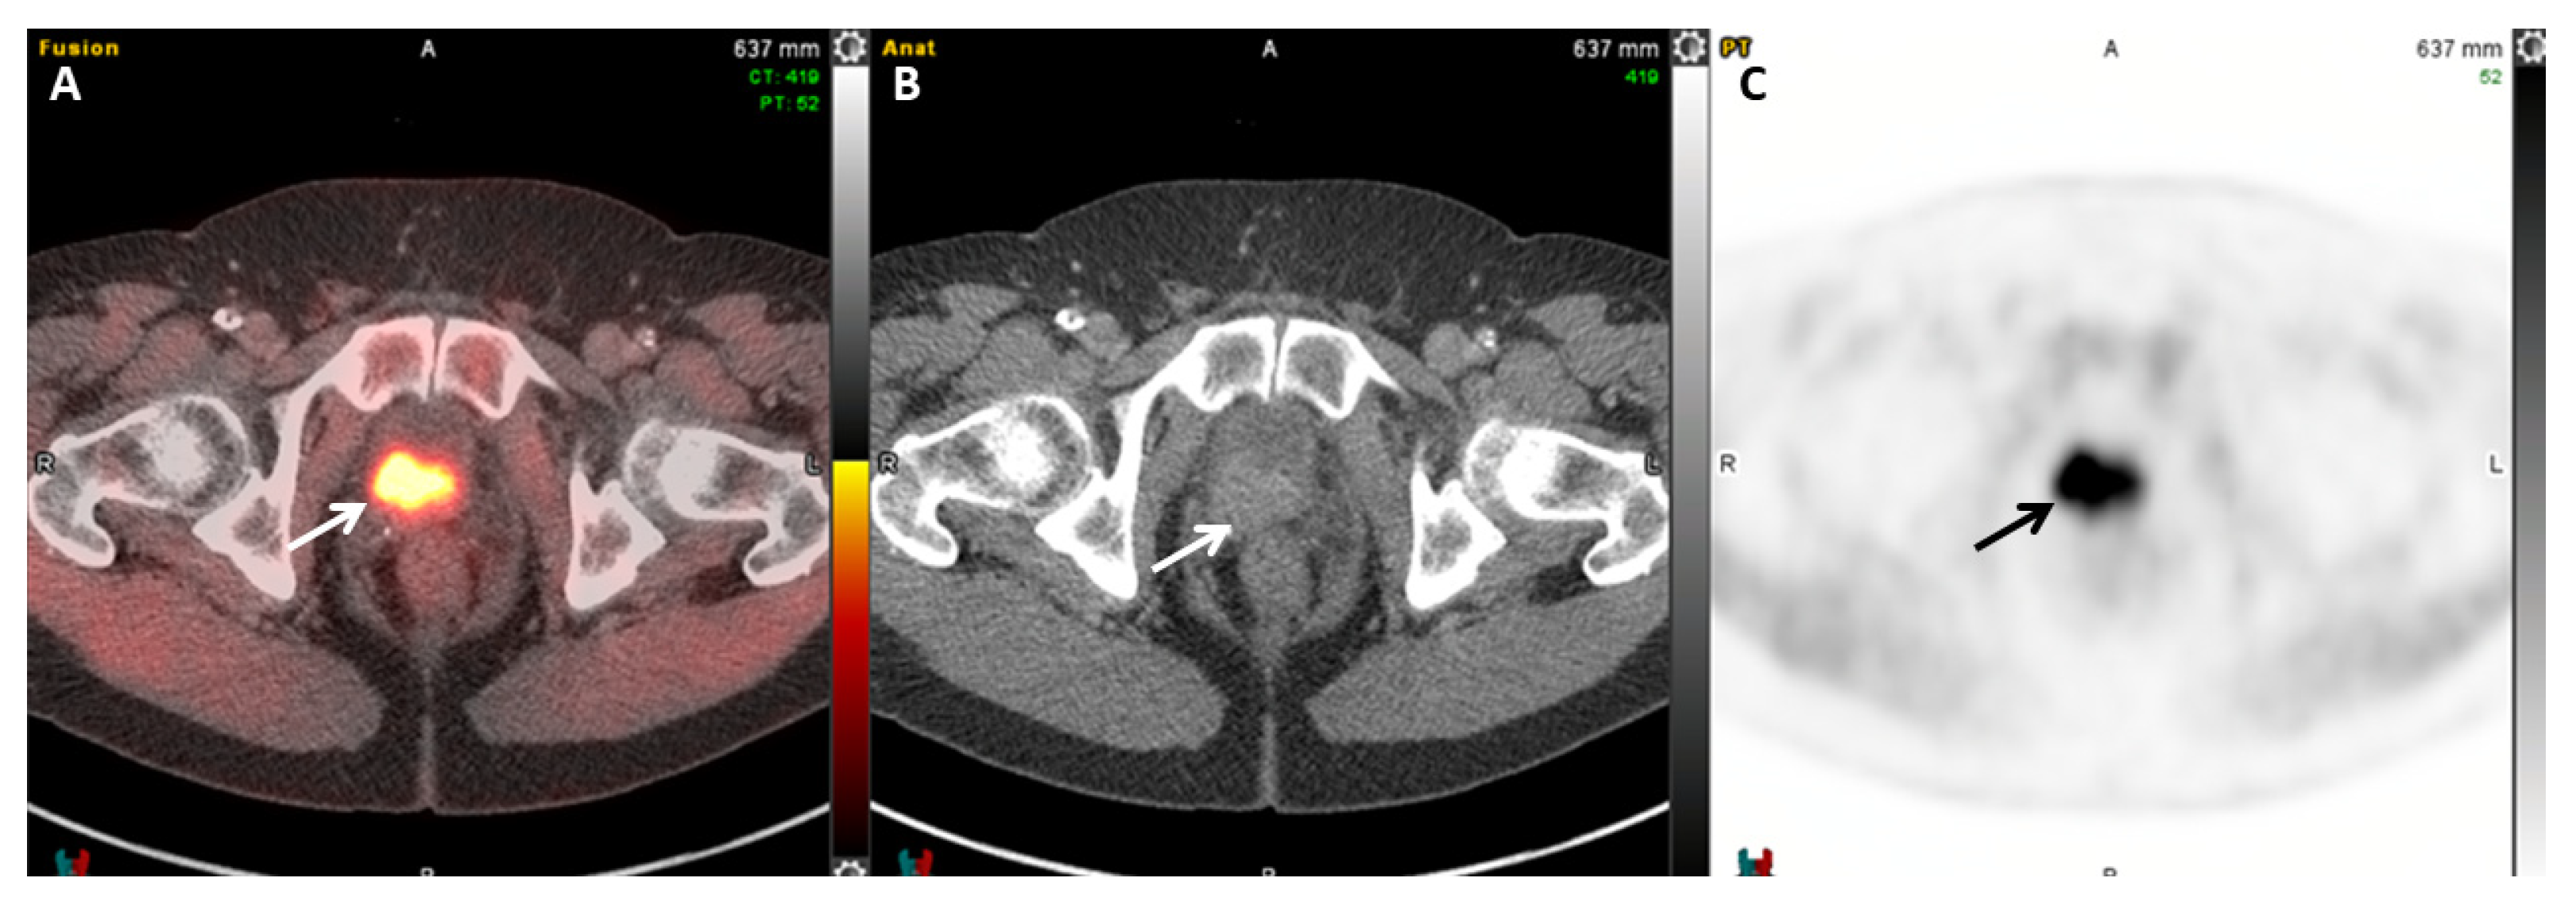

2.5.5. 18F-PSMA-1007